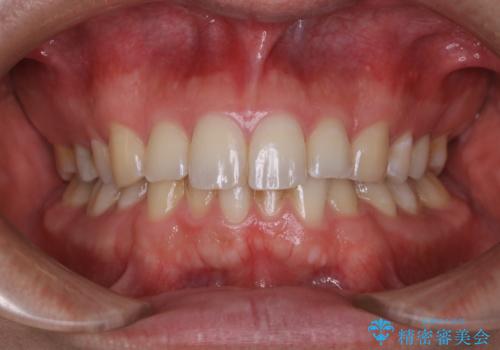

コーヒーの着色落としをPMTCでキレイに

- コーヒが好きで、ステインが付くことが気になるとのことで来院されました。PMTC30分コースを行いました。